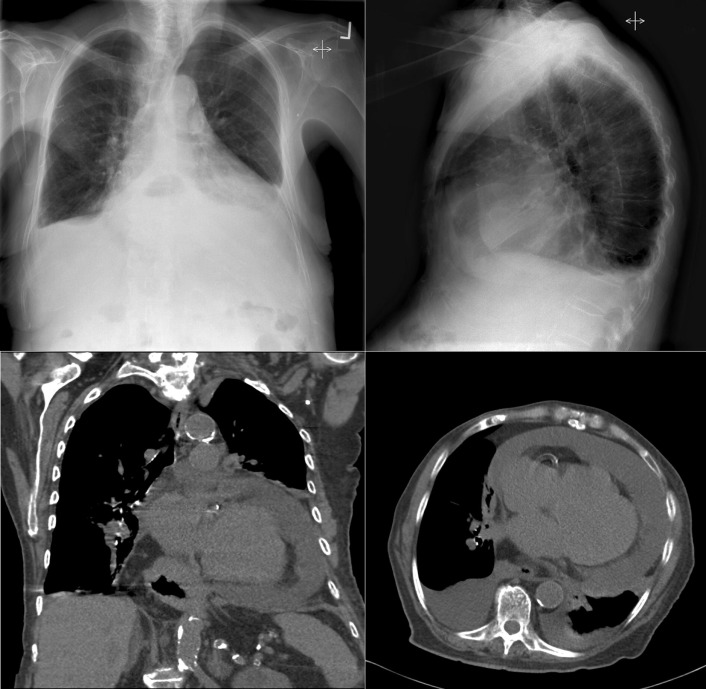

A pericardial effusion ( Figs. 16-1 to 16-15 ) is often suggested on the frontal chest radiograph by a smoothly distended, “flasklike” CPS. More than 500 mL of fluid must be present before the change in the CPS is fairly obvious. A flasklike appearance may be caused by myocardial disease as well; scrutiny of the hilar vessels may distinguish the two. In the presence of pericardial effusion, the hilar vessels are covered (the pericardium runs up onto them and obscures them). In the presence of myocardial disease, the hilar vessels are unusually prominent as they are distended under higher than usual pressure.

In a minority of patients with pericardial effusion, on the lateral radiograph, a stripe of radiolucent epicardial fat, a “fat line,” may be visible anteriorly, suggesting fluid in the pericardial space. A stripe greater than 2 mm is abnormal. This “pericardial stripe sign” is more easily seen in adults than children (more fat!).

A prominent azygous vein, superior vena cava, or inferior vena cava suggests cardiac tamponade.

Echocardiography is the diagnostic test of choice for the evaluation of pericardial effusions. Pericardial tamponade remains a clinical diagnosis, strengthened by supportive echocardiographic findings.